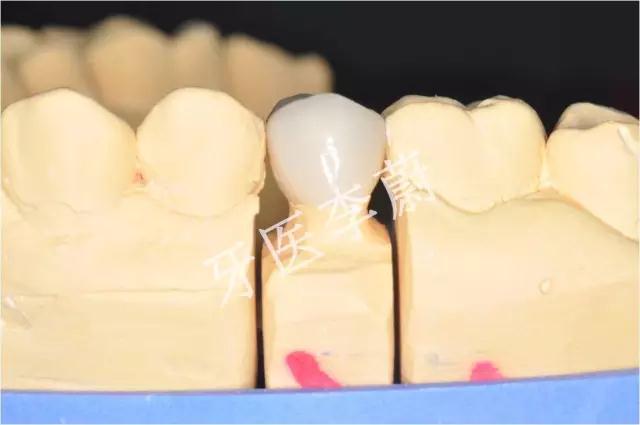

15牙模型

15牙二氧化锆烤瓷冠舌面观

15牙二氧化锆烤瓷冠颊面观